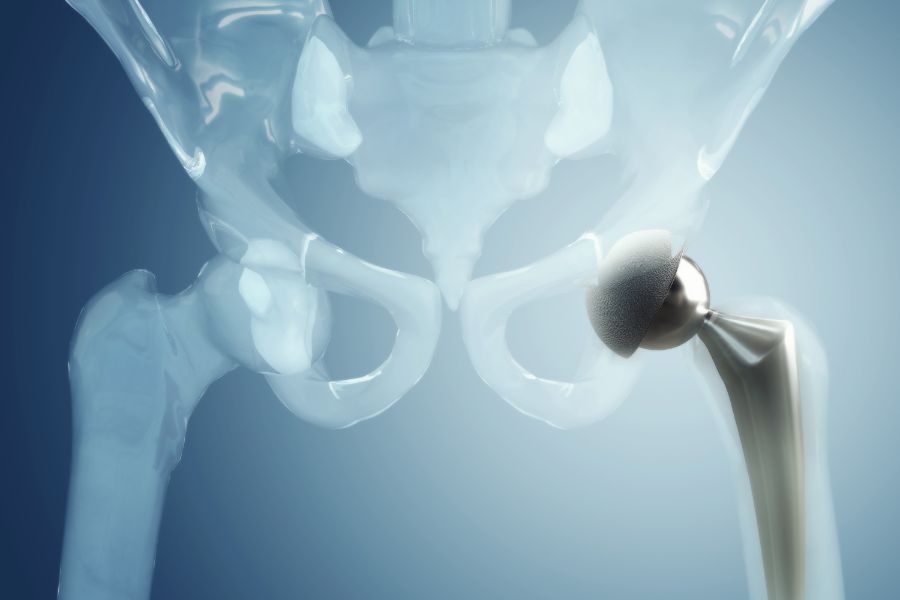

Kalça protezi, kalça eklemindeki ciddi hasarları gidererek ağrısız ve hareketli bir yaşam sunan etkili bir cerrahi yöntemdir. Ancak zamanla bu protezler gevşeyebilir, aşınabilir ya da enfekte olabilir. Böyle durumlarda kalıcı çözüm için kalça protezi yenilenmesi, yani revizyon cerrahisi gerekebilir. Bu işlem, ilk uygulanan protezin çıkarılarak yeni ve sağlam bir protezle değiştirilmesini kapsar. Bu yazıda kalça protezi revizyonu nedir, neden ihtiyaç duyulur, belirtileri nelerdir ve hangi tedavi seçenekleri uygulanır, tüm detaylarıyla ele alıyoruz.

Kalça protezi yenilenmesi, daha önce takılmış olan kalça protezinin çeşitli nedenlerle işlevini yitirmesi sonucu, protezin tamamının ya da bir bölümünün çıkarılarak yenisiyle değiştirilmesidir. Revizyon cerrahisi, ilk ameliyata göre daha karmaşık ve uzun süren bir işlemdir çünkü kemik kaybı, yumuşak doku hasarı veya enfeksiyon gibi durumlar cerrahiyi teknik açıdan zorlaştırabilir. Buna rağmen başarılı bir revizyon işlemiyle hasta yeniden ağrısız ve aktif bir yaşama dönebilir.